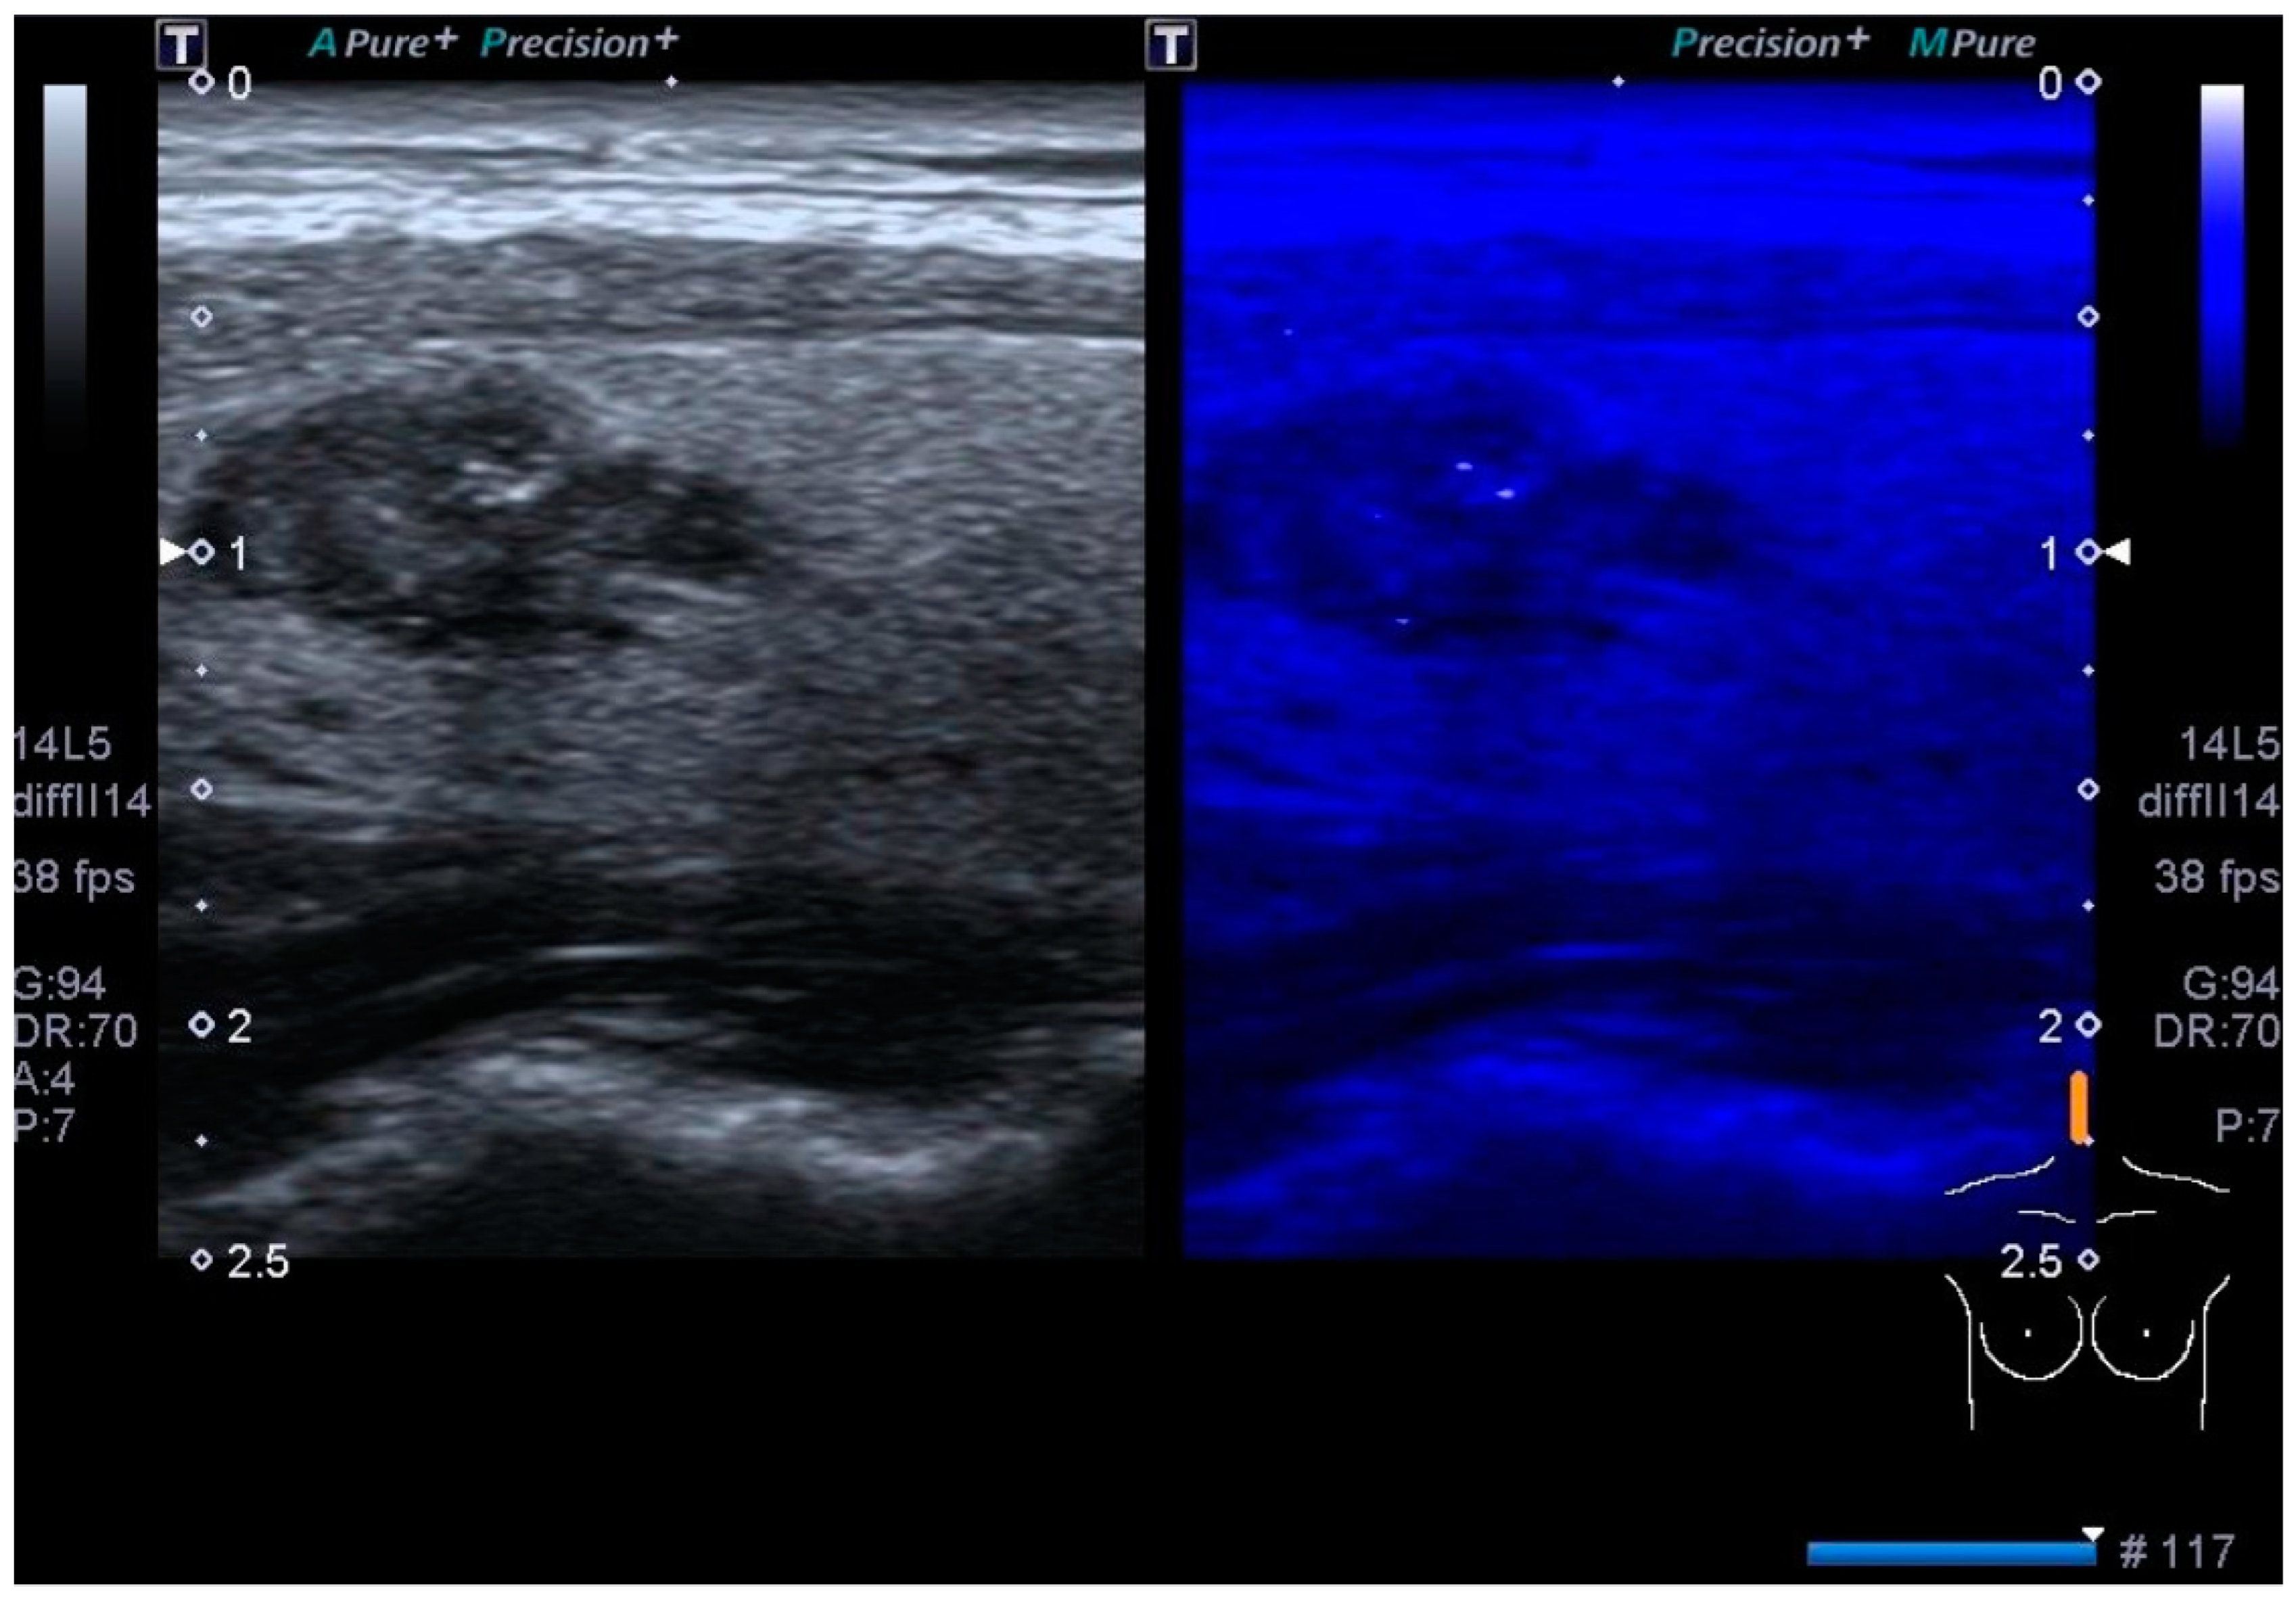

3.2. Color Doppler US

3.3. Contrast-Enhanced US

3.4. Elastography